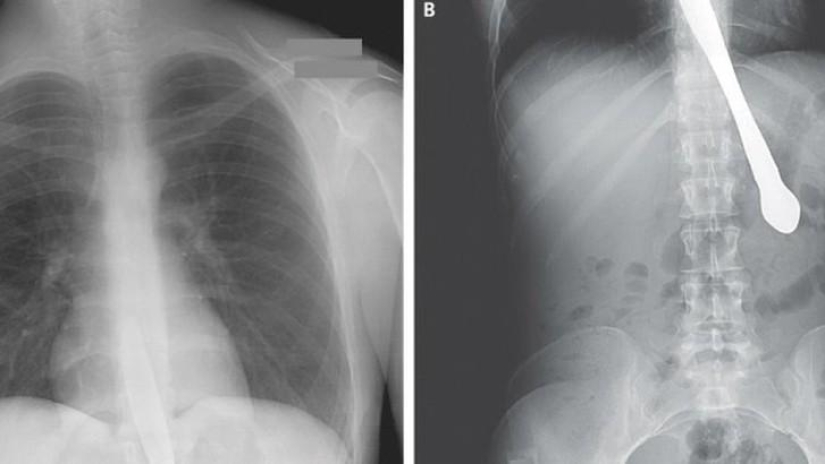

21. La hélice del avión.

22. Pinzas quirúrgicas.